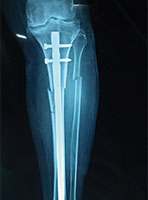

Case 4: Tibial Fracture

70 Years female fell in the bathroom and sustained injury to his left leg. She had fracture of left leg (tibia and fibula)

X-RAY 1

Pre operative x-ray showing fracture both bone left leg

X-RAY 2

Post operative Xray

X-RAY 3

Post op xray tibial fracture fixed with interlocking nail